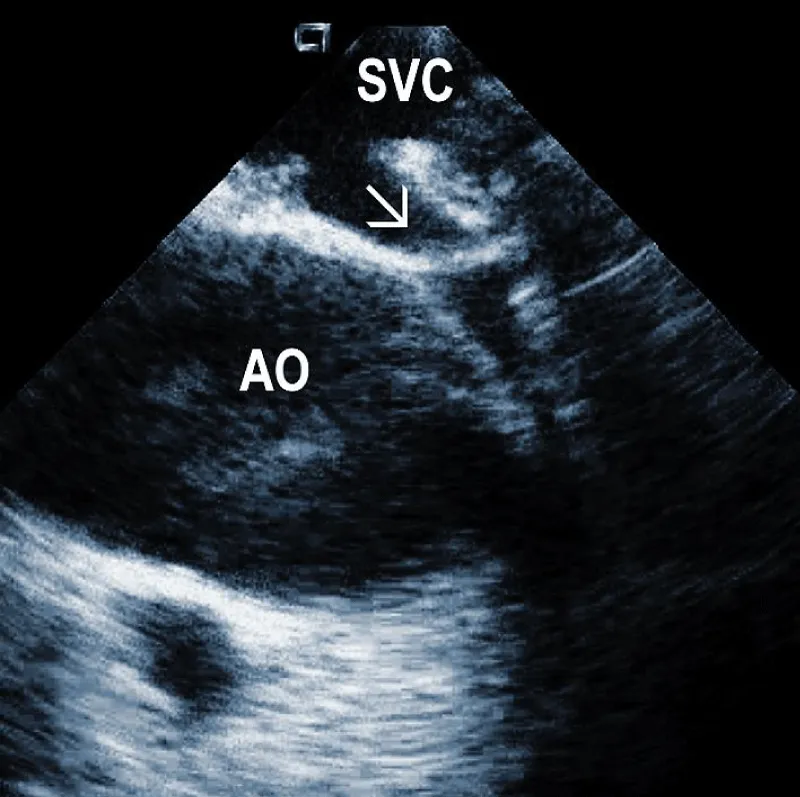

Figure 3A: Fibrous adherences (arrow) attaching the lead within the superior vena cava (SVC). AO: Ascending aorta.

Areas of fibrous adherence: Areas of fibrous adherences or attachments (i.e., scar tissue) can be visualized as echo-dense structures along the lead course (Figure 3A). Multiple leads are usually attached by fibrous tissue together (Figure 3B). The location of fibrous adherence can be anywhere in the course of the lead [7,10]. In a study by Bongiorni, et al. [7], scar tissue was noted by ICE in the subclavian vein, innominate vein, and the right ventricle in about 80%, 68%, and 68% of cases, respectively. Sadek, et al. [10] described attachments less frequently – only in 18/50 pts (36%), predominantly intracardiac. Anecdotal cases were reported on specific locations of adhesions, such as a vulnerable “stalk” attaching the papillary muscle to the RV endocardium [18]. Notably, the fibrous attachment presence correlated with the extraction procedure’s difficulty. These patients were more likely to have a “complex” extraction procedure. Subjects who did not have evidence of lead attachment were less likely to require the advancement of the extraction sheaths past the superior vena cava and less likely to require advanced extraction tools such as snares.

Another study, using an IVUS catheter introduced to the superior vena cava region, attempted to classify intravascular lead adherences [19]. Adherences were assorted into three categories based on three criteria: 1) lead mobility, 2) lead proximity to the vessel wall, and 3) presence of lead-onlead binding [8]. The categories were as follows: (grade 1) free-floating leads or only intermittently adjacent to the vessel wall and minimal inter-lead binding; (grade 2) leads with restricted mobility, frequently adjacent to the vessel wall with moderate lead-to-lead binding, (grade 3) immobile leads attached to the wall with significant lead-to-lead binding. Grade 1 and 2 are also classified as low grades, and grade 3 as high with elevated risk. This grading system correlated with extraction difficulty.

In addition, ICE imaging may improve the identification of patients at higher risk of superior vena cava tear. However, further studies are needed. Some operators recommend using a prophylactic vascular occlusion balloon in case of SVC adhesions [10,20]. Another option for such cases to decrease the risk of damage to the SVC is a countertraction from below [21].